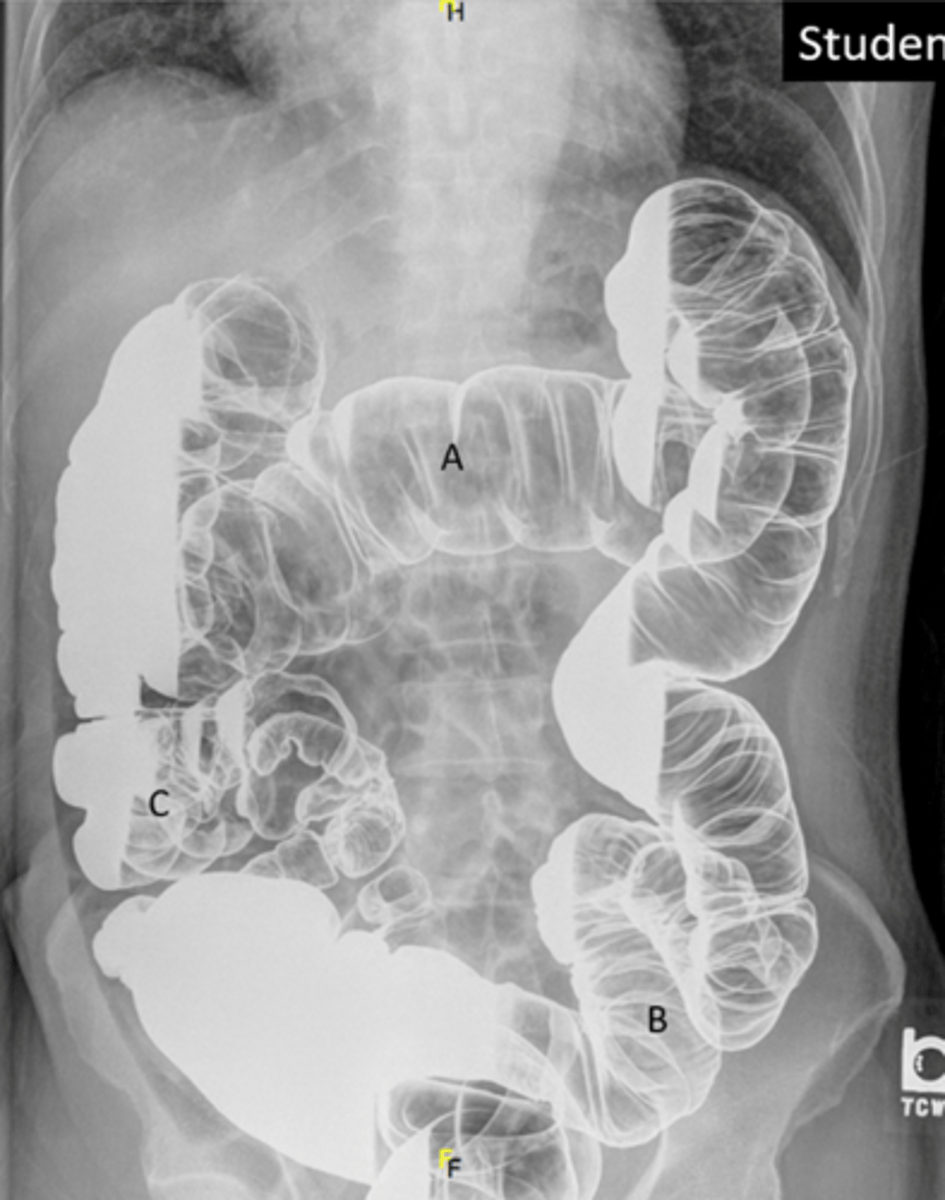

Identify indicated anatomy in the following radiograph

A: transverse colon

B: Sigmoid Colon

C: Cecum

F: Rectum

<p>A: transverse colon</p><p>B: Sigmoid Colon</p><p>C: Cecum</p><p>F: Rectum</p>